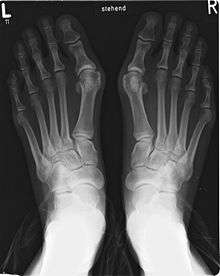

Bunion

A bunion is a deformity of the joint connecting the big toe to the foot. It is characterized by medial deviation of the first metatarsal bone and lateral deviation of the hallux (big toe), often erroneously described as an enlargement of bone or tissue around the joint at the bottom of the big toe (known as the metatarsophalangeal joint).

Bunions are commonly associated with a deviated position of the big toe toward the second toe, and the deviation in the angle between the first and second metatarsal bones of the foot. The small sesamoid bones found beneath the first metatarsal (which help the flexor tendon bend the big toe downwards) may also become deviated over time as the first metatarsal bone drifts away from its normal position. Arthritis of the big toe joint, diminished and/or altered range of motion, and discomfort with pressure applied to the bump or with motion of the joint, may all accompany bunion development. Atop of the first metatarsal head either medially or dorso-medially, there can also arise a bursa that when inflamed (bursitis), can be the most painful aspect of the process.